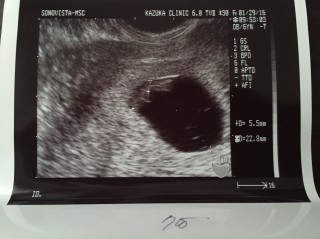

心拍が確認できると思って行ったら、先生は見えるような気もするけど、うーん。まぁ次で見えるでしょう。(心配なし)という反応でした。 とは言え、サイズも5ミリとネットで見るととても心配。。 ただ、この後8週できちんと成長していて、心拍も聞こえました。なので、ネットに振り回されてはいけないなと思いました。